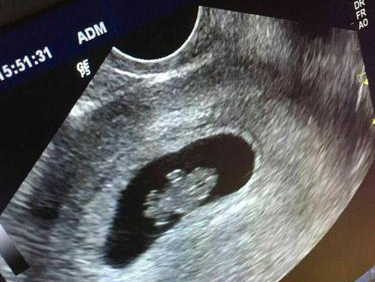

眾所周知,高齡懷孕的風險是比較高的,尤其是像47歲已經瀕臨絕經的年齡,這個年齡考慮懷孕的女性備孕是非常艱難的,但也有一些女性懷上之後,但不知道該怎麼辦,今天本文就特地為大家帶來了高齡懷孕的保胎技巧。47歲懷孕怎麼辦47歲的女性在懷孕後,首先要到醫院檢查是否是宮內孕,如果是宮外孕的話就需要選擇終止妊娠,所以在停經40天以上去醫院檢查B超,明確是否是宮內孕以及胎囊、胎芽的大小,然後再進行保胎。如果是宮...